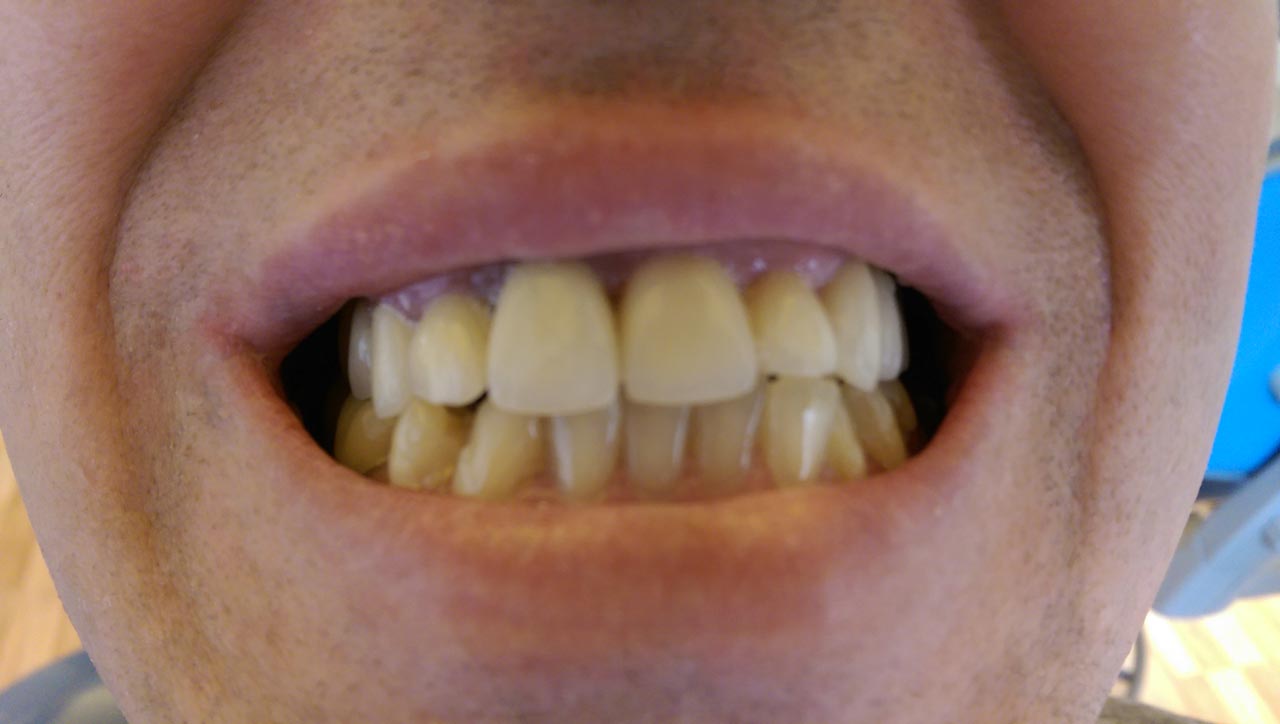

Elhanyagolt fogsor cseréje 2 nap alatt

2 nap alatt varázsoltuk ezt a szép esztétikus alsó, felső körhídat implantátumokkal megtámasztva a korábban elhanyagolt szájba. Az 1. nap 26 fogat távolítottunk el, mert annyira rossz állapotban voltak, és rögtön azonnal terhelhető IHDE svájci implantátumokat raktunk be, fentre 8, lentre 6 darabot. A sebeket összevarrtuk és intraorális szkennerrel digitális lenyomatot vettünk. 2 nap múlva pedig beragasztottuk a kész PMMA műanyag körhidakat. Dr. Kelemen Péter és a Symbion Fogtechnika munkája.